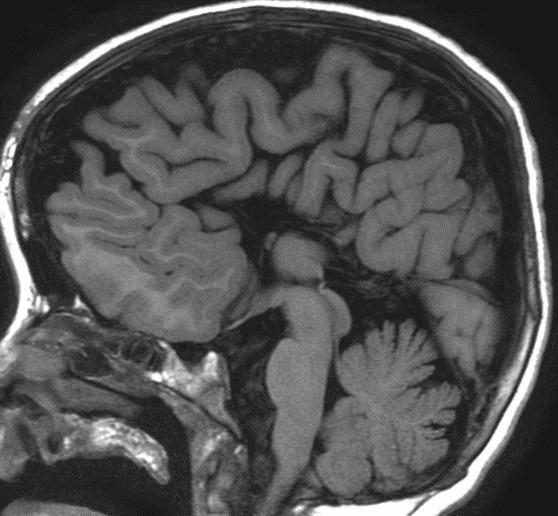

Sweep the Midline…Name the parts…where do we start?

Sag T2 Cube nongated Normal

Normal

Sag T2 Cube

Nongated: CSF dephasing in the aqueduct on this sequence

Primary fissure 3 lobes Closed fastigial point

Sag T2 Cube Normal

Anterior commissure

Corpus Callosum

Rostrum, genu, body, splenium

Sella/Suprasella

ON, post pit bright spot, stalk

Midbrain

Patent aqueduct

Pons

“just right…”

Vermis

3 lobes

Cerebellar Tonsils